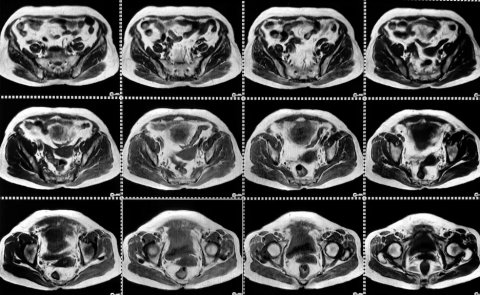

Ce collectif rassemble des expertises en apprentissage automatique, aide à la décision, IA symbolique, recherche opérationnelle et automatique. Les travaux portent notamment sur le développement de modèles robustes et adaptatifs dans des contextes marqués par l’incertitude, la dynamique et la collaboration Homme-Machine. L’objectif est de garantir la fiabilité et la transparence de l’IA dans des domaines sensibles tels que la santé ou l’industrie 5.0, en apportant les bases d’une adoption responsable et durable de l’IA.

- Rayane ELIMAM. Apprentissage automatique pour la prédiction de performances : du sport à la santé. Sous la direction de Jacky Montmain et Stéphane Perrey. Accéder à la thèse : https://theses.fr/2024EMAL0005

- AJRA Zaineb. Modèles neurophysiologiques dynamiques et apprentissage profond pour l'étude de la connectivité cérébrale de sujets sains et cérébrolésés. Encadrement de thèse : Jacky Montmain, Stéphane Perrey. Accéder en ligne : https://www.theses.fr/s296504.

- LOPES DE SOUZA Victor. Classification prudente de la réponse individuelle à la rééducation post-AVC. Direction de thèse : Abdelhak Imoussaten, Sofiane Ramdani.